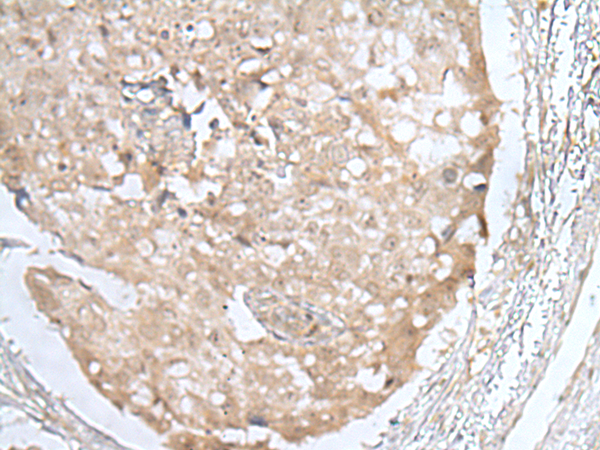

IHC (Immunohistochemistry)

(Immunohistochemistry of paraffin-embedded Human lung cancer tissue using HOXD3 Polyclonal Antibody at dilution of 1:25(×200))